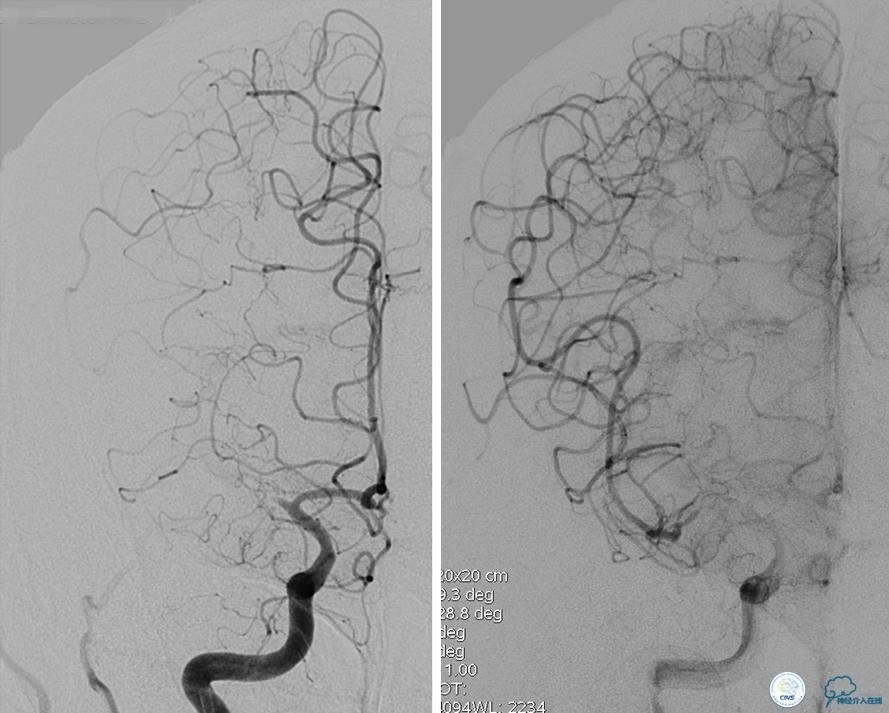

患者:49岁女性,脑梗死30天。

左侧颈内动脉末端闭塞,末端圆钝且有一定成角,开通难度较大,多次尝试导丝才成功穿过闭塞段。

开通效果很满意,术后症状明显恢复。